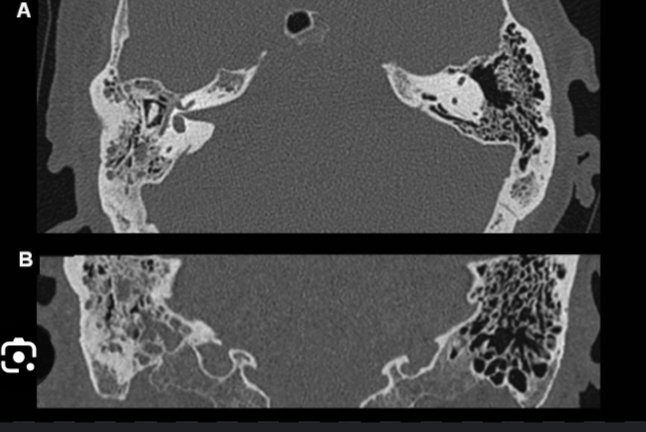

8

Otomastoiditis